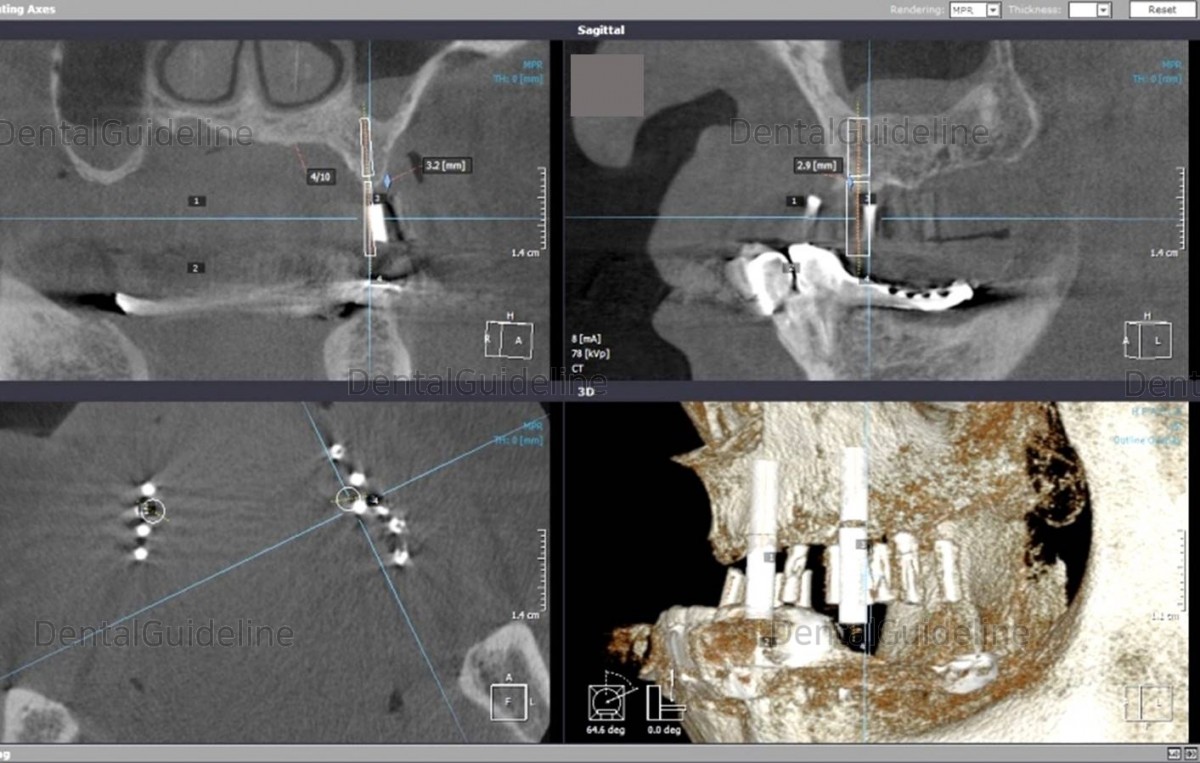

Check the angle between the two implants on the radiograph